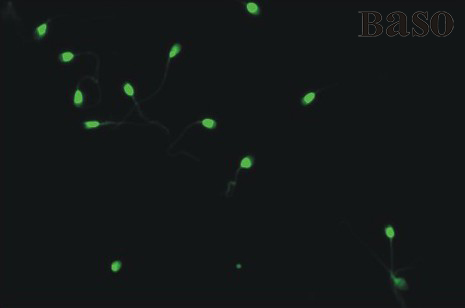

精子DNA染色試劑盒(吖啶橙法)

詳細(xì)資料

PDF